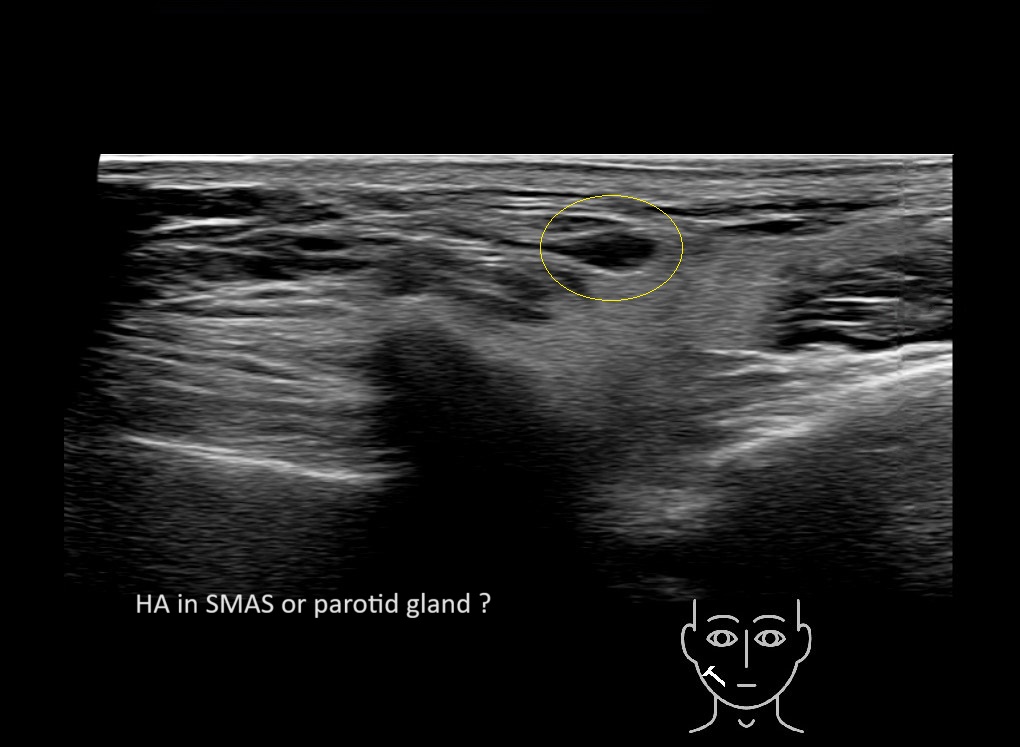

Filler injections in the parotid gland may go unnoticed, however, inflammatory reactions and abscesses may occur. Hypervascularity can be seen with color doppler. Filler deposits are supposed to be injected into the superficial fatty layer . The space to inject into this layer may be limited. Routinely we measure a width of 2-4 millimeters with sometimes subcutaneous layers being less than one millimeter thick.

Study the first image to recognize the different layers. If you are sure about the layers, swipe to the second image to view the answer (if applicable).